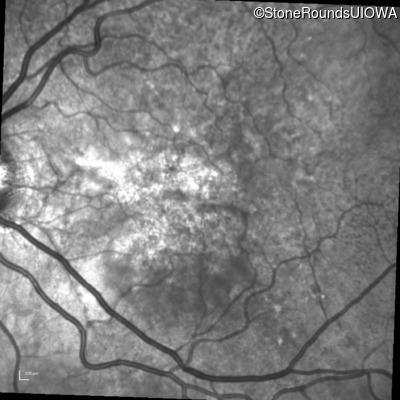

Infrared Fundus Photograph - Right - 20/20 -3 sc

Exemplar

Infrared Fundus Photograph - Left - 20/30 -2 sc